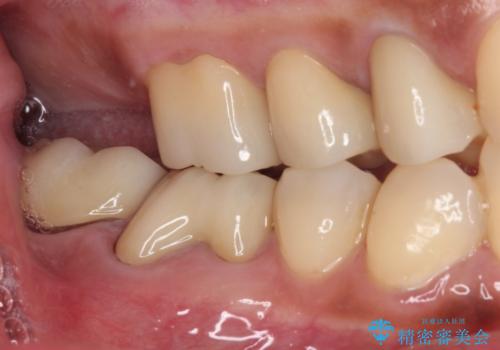

- 奥歯を治療しようと他院で開始したものの、放置してしまったとのことで来院された患者様です。

外れてしまった銀歯や穴の空いた仮歯などあり、適合の悪い被せものと合わせて、セラミッククラウンやセラミックインレーにて治療と行うこととしました。

億劫に感じて治療を先延ばししていたそうですが、始めてみるとスムーズに治療が終わり、早く始めておけば良かったと仰っていました。

他にも加療の必要な歯があるので、定期健診を行いながら再開していく予定です。